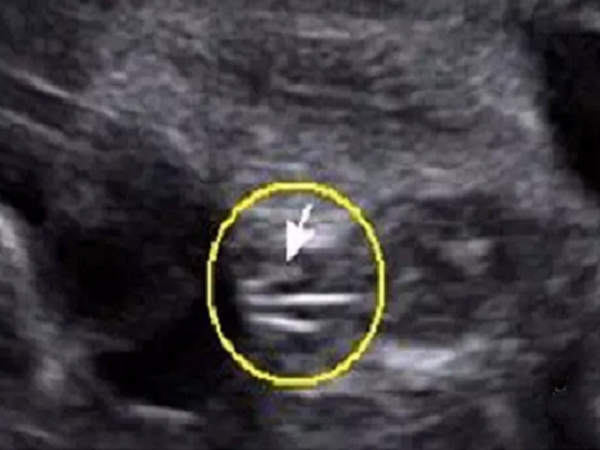

三条线

胎儿的双腿之间,若是能看见三条线,且两腿中间有小凹槽,则一般是女孩,若是能看见有亮点,且双腿中间有小凸起,则一般是男孩。